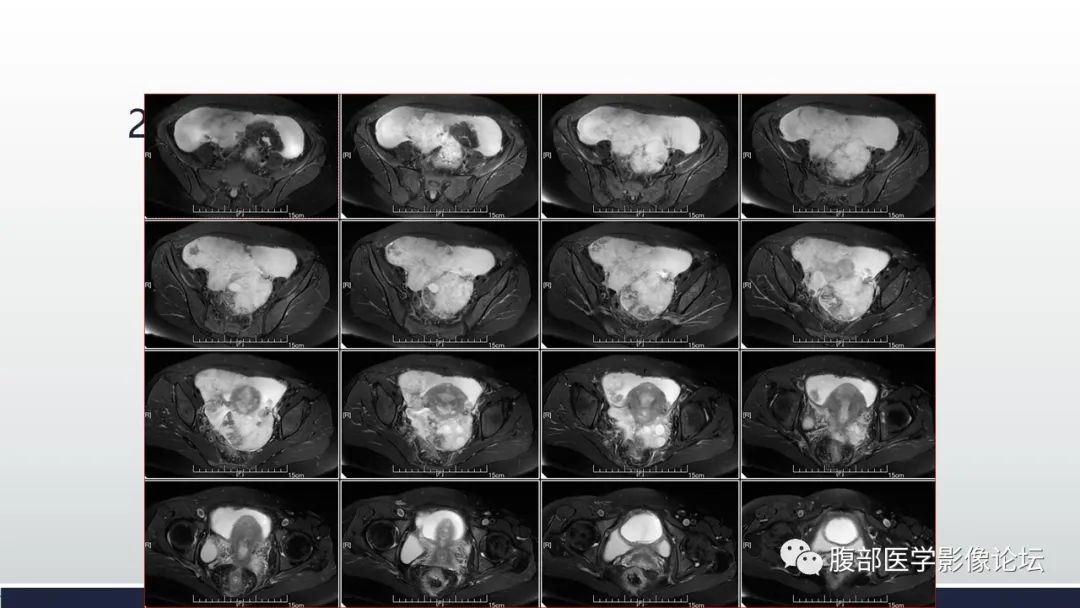

【病例】子宫内膜透明细胞癌1例MR-3

【病例】子宫内膜透明细胞癌1例MR-4